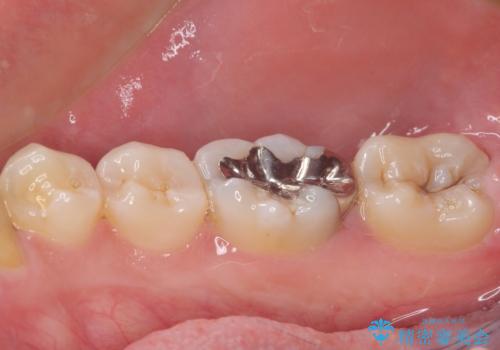

- 矯正治療後に目立つ銀歯を白くしたいとのことで来院された患者様です。

左上の銀歯は、銀歯の下に金属の土台が入っているため、その土台を除去し、ファイバーコアにやり替えて、オールセラミッククラウンにて補綴することとしました。